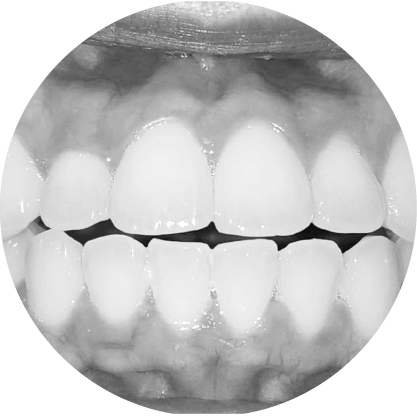

ตัวอย่างในชีวิตจริง